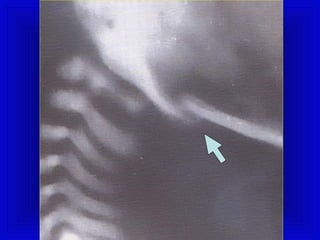

PPHHRREENNIICC NNEERRVVEE PPAARRAALLYYSSIISS

• The diagnosis